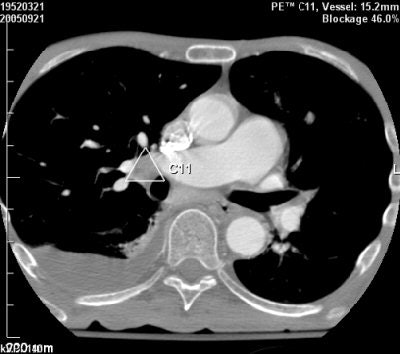

| Above, false-negative PE finding, missed by CAD system and added manually by the radiologist. Below, perivascular soft tissue that produced a false-positive PE finding from CAD. Images courtesy of Dr. Zeev Maizlin and Dr. Peter Cooperberg. |

![]() |